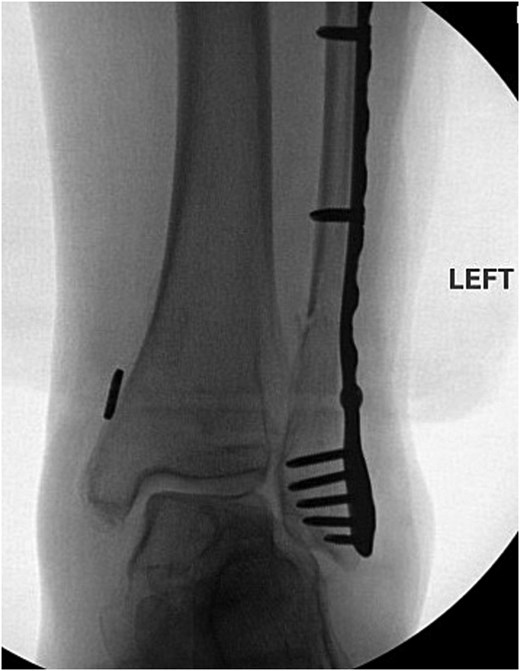

The lateral malleolus Weber C fracture was subsequently reduced to anatomical position. A locking stainless-steel plate was pre-contoured for the patient’s fibula and placed along the right lateral malleolus. Two 3.5 mm fully threaded bi-cortical locking screws were placed above the fracture and another 3.5 mm fully threaded bi-cortical locking screw was placed at the proximal end of the plate. A total of five 2.7-mm uni-cortical locking screws were used for fixation below the fracture site. Fluoroscopic images of the right ankle were taken in three views with simulated weight bearing in order to confirm anatomic alignment of the lateral malleolus Weber C fracture with proper plate and screw fixation. The syndesmosis was stressed in order to assess deltoid ligament function which showed widening. The distal tibiofibular joint was debrided and a king tong clamp was placed across the tibia and fibula through the fibular plate. Dorsiflexion of the ankle and hanging the posterior heel off a bump was done to avoid any anterior drawer effects on the ankle; following such, a tightrope was placed. Following final imaging (Fig. 3), the wound was then closed in layers.

Anterior–posterior post-operative X-ray demonstrating fixation of right Weber C fibular fracture.